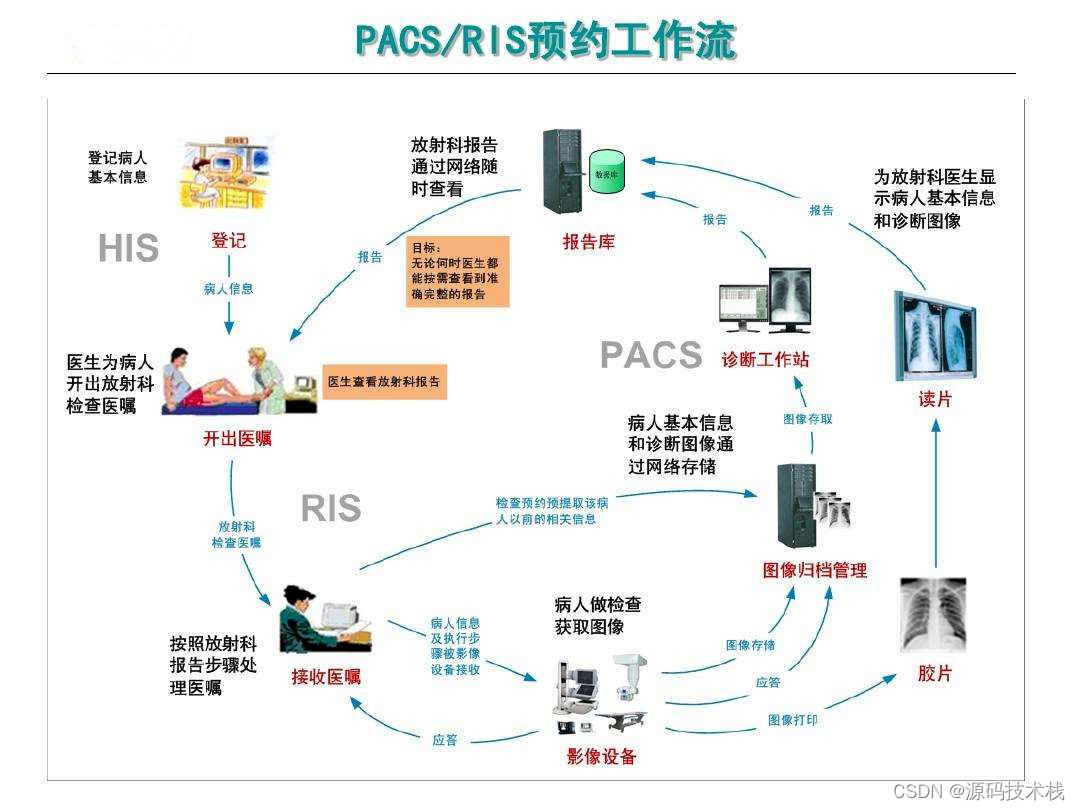

PACS主要包括图像获取、图像传输、图像储存和管理、图像影像工作站进行阅读四个流程。临床上,PACS系统流程从患者在登记台登记检查开始,然后患者进入检查室,技师进行检查,采集影像数据,将采集的影像数据进行上传至PACS网,影像医师通过PACS调阅图像并书写报告,最后将PACS的图文报告归档。

2、RIS

放射信息管理系统。主要有登记预约、排队叫号、技师模块、报告模块、主任模块、采集模块等模块。

Scheduled Workflow Integrated Profile(简称SWF集成方案)。该集成方案是整个IHE信息框架的基础,依托于DICOM3.0标准,顺利解决了HIS、RIS、PACS和数字化影像设备(Digital Imaging Modality)之间的信息传输。